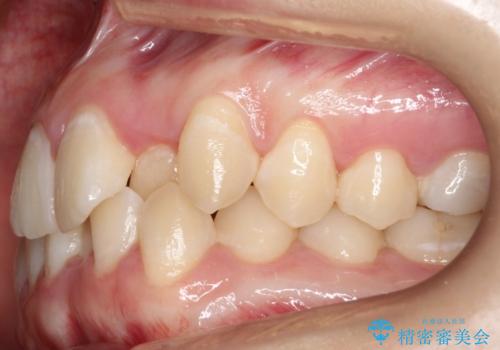

前歯が前後反対にかんでいる インビザラインによる矯正

- 前歯のがたつきを気にされて来院されました。

上顎の前から二番目の歯が内側に入り込んでおり、前後反対にかんでいる状態でした。

歯と歯の間にわずかに隙間を作り並べる計画としました。

しっかりとマウスピースを使用していただけたので、順調に治療を終えることができました。